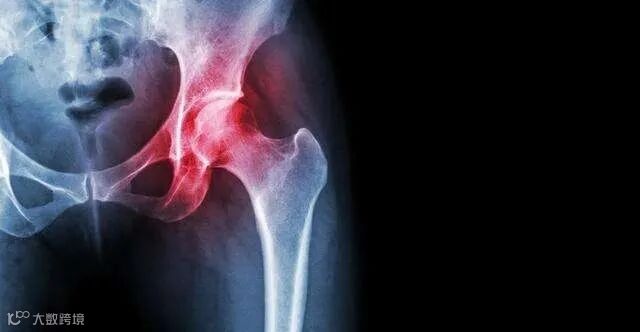

股骨头坏死( ONFH) 又称股骨头缺血性坏死,是骨科常见疾病。股骨头坏死主要是由于股骨头血供受损,进而引起软骨下骨折、股骨头变形塌陷、髋关节骨性关节炎致髋关节功能障碍的进展性疾病。近年来随着激素及酒精的大量使用,该疾病趋年轻化,且发病率稳中有升。

无论是哪种致病因素,最终均导致股骨头血液供应受到破坏,缺血区骨细胞及软骨细胞变性坏死,股骨头内出现微骨折。

由于缺血状态持续存在,组织修复能力下降,最终出现股骨头塌陷及髋关节骨性关节炎,并导致关节疼痛及功能障碍,进而出现负重和行走功能障碍。发病早期较为隐匿,容易导致干预不及时而加重病情。